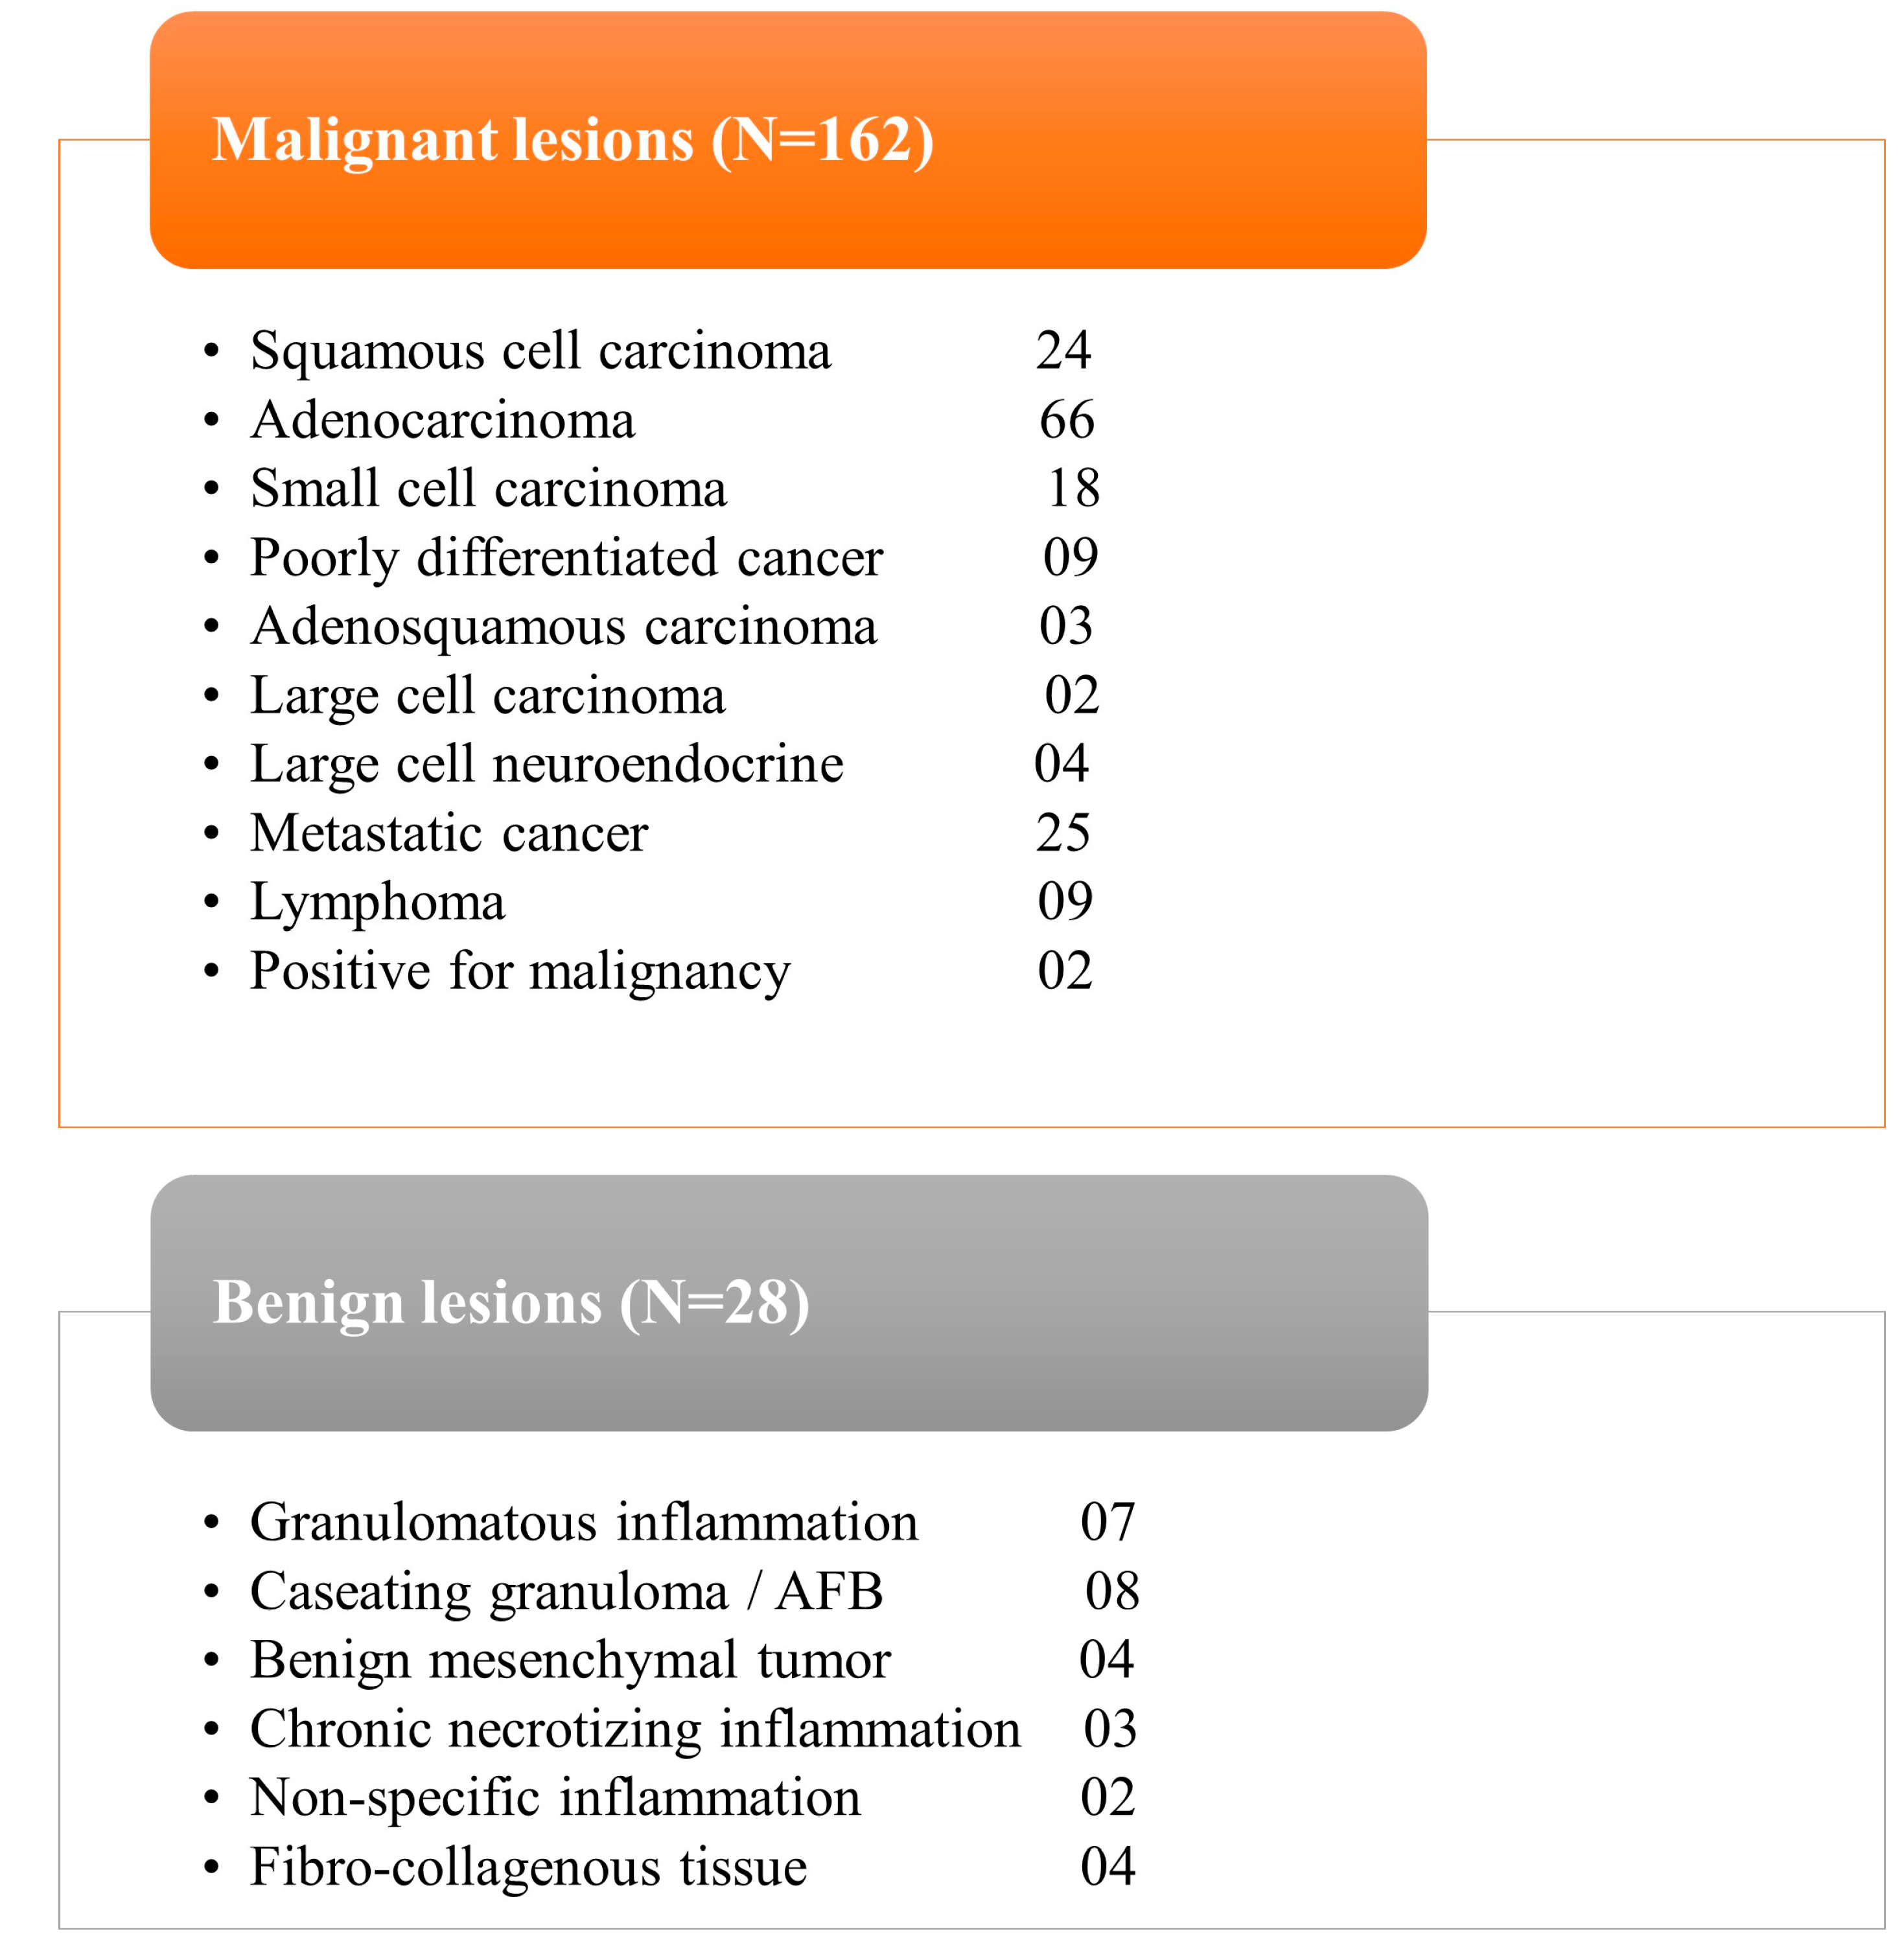

Figure 1. Except for two individuals, sufficient samples were acquired from all patients. These two individuals received positive diagnoses of cancer but inadequate material for further IHC characterisation. Histopathological study reveals that 162 (85%) of the lesions were malignant and 28 (15%) were benign (

Figure 2), including inflammatory cells, necrotic tissue, and infection. The patients with benign results were appropriately treated based on histology findings and monitored for at least 6 months to rule out disease development. Four biopsies (2.1% of total) yielded non-specific results and were deemed non-diagnostic. The overall diagnostic yield of metabolic biopsy in our study was 96.9%. Among the 190 metabolic biopsies performed in our study, the rate of complications (major and minor) was 13.1% (25 patients), with the greatest number occurring in patients with lung lesions (21 patients). Two individuals had life-threatening complications that contributed to their deaths (one individual had a large perihepatic hematoma and the other individual had large volume haemoptysis). The patient with severe haemoptysis had numerous coexisting morbid conditions.